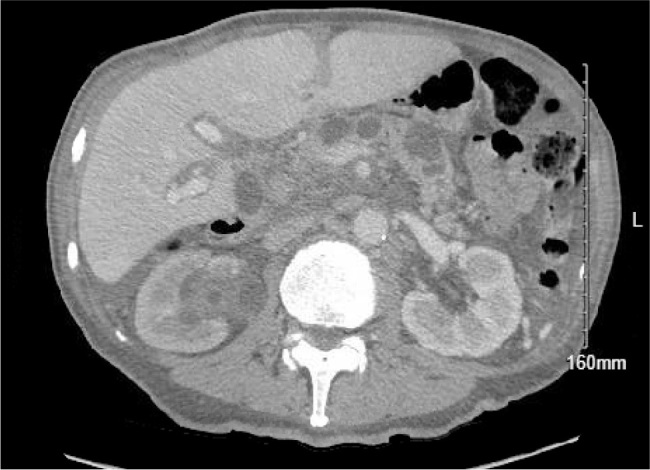

自身免疫性溶血性贫血(AIHA)是由抗体介导的红细胞破坏引起的。AIHA有两大类:温热型和冷热型,都是根据自身抗体的热反应性来分类的。冷凝集素病(CAD)发生在温度低于正常体温,主要涉及IgM抗体。CAD通常继发于其他疾病:淋巴增生性疾病或感染,尽管它很少是特发性的。我们报告一例65岁男性,无既往病史,最初表现为血尿和蛋白尿,伴血小板减少症和白细胞减少症。他报告体重意外减轻超过9公斤,便秘,大便呈浅油腻色。腹部和骨盆的计算机断层扫描显示可疑的原发性胰腺肿瘤伴淋巴结转移和早期癌,严重的右侧肾积水和胆囊扩张。直接抗球蛋白试验(DAT)筛选为阴性,但抗体筛选为阳性。患者冷凝集素筛查阳性,CA 19-9、癌胚抗原(CEA)和环瓜氨酸肽(CCP)水平升高,这些肿瘤标志物通常用于诊断胰腺癌。患者的症状和实验室结果提示溶血性贫血与疑似实体器官恶性肿瘤(特别是胰腺癌)之间存在复杂的相互作用。他的肿瘤标志物升高,抗体筛查和凝集素冷筛查呈阳性,提示可能继发于胰腺癌的副肿瘤综合征。然而,他的感染和自身免疫小组的发现使情况进一步复杂化,并强调了他的病情的多因素性质。学习要点:本病例强调了自身免疫性溶血性贫血(AIHA)与胰腺腺癌之间的罕见关联。虽然AIHA是一种已知的血液系统恶性肿瘤的副肿瘤综合征,但本病例报告表明它也可能是实体肿瘤的副肿瘤综合征。本病例报告强调了在合并症的情况下治疗AIHA的困难,表明标准治疗指南可能无效。

Autoimmune haemolytic anaemia (AIHA) is caused by antibody-mediated destruction of red blood cells. There are two broad categories of AIHA: warm and cold, both categorized by the thermal reactivity of the autoantibodies. Cold agglutinin disease (CAD) occurs at temperatures below normal body temperature and primarily involves IgM antibodies. CAD typically occurs secondary to other processes: lymphoproliferative disorders or infection, although it can be rarely idiopathic. We present a case of a 65-year-old male with no past medical history who initially presented with haematuria and proteinuria, along with thrombocytopenia and leukopenia. He reported an unintentional weight loss of more than 9 kg, constipation, and pale-greasy coloured stools. Computed tomography (CT) scan of the abdomen and pelvis revealed findings suspicious for primary pancreatic neoplasm with nodal metastases and early carcinomatosis, severe right hydronephrosis, and distended gallbladder. Direct antiglobulin test (DAT) screening was negative, but an antibody screen was positive. The patient had a positive cold agglutin screen and elevated CA 19-9, carcinoembryonic antigen (CEA), and cyclic citrullinated peptide (CCP) levels, tumour markers used typically for diagnosis of pancreatic cancer. The patient presented with symptoms and laboratory findings suggestive of a complex interplay between haemolytic anaemia and a suspected solid organ malignancy, specifically pancreatic cancer. His elevated tumour markers and positive antibody screen and cold agglutinin screen suggested the possibility of paraneoplastic syndrome secondary to his pancreatic cancer. However, his infectious and autoimmune panel findings further complicated the picture and underscored the multifactorial nature of his condition.